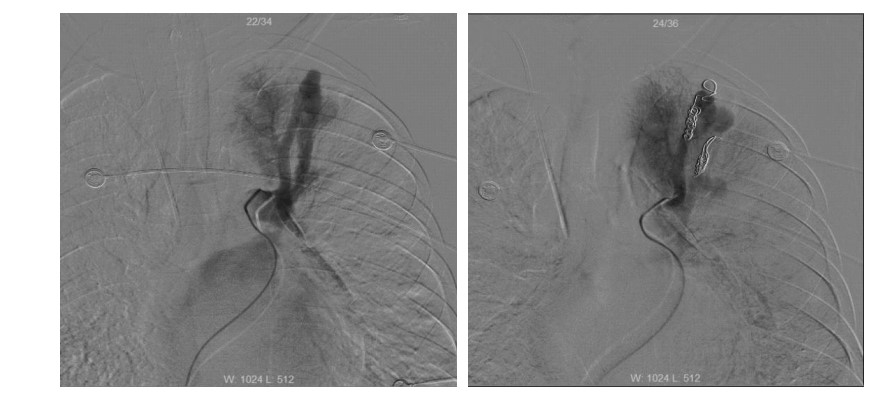

患者男性,25岁,因“突发抽搐后摔倒3 h余”于2014年2月23日诊断“外伤性硬膜下血肿”入我院神经外科,否认既往重大疾病史。急诊头颅计算机断层扫描(computed tomography,CT)及核磁共振成像(magnetic resonance imaging,MRI)均提示“左侧额颞部少量硬膜下血肿”。入院时患者浅昏迷,躁动不安,格拉斯哥昏迷评分(glasgow coma scale,GCS)11分,双侧瞳孔等大,光反射灵敏,两肺听诊未闻及明显干湿啰音,心律齐,无明显杂音,四肢均有活动,杵状指。入院后患者氧饱和度偏低,不吸氧时指脉氧饱和度波动在85%~90%之间,血常规:白细胞计数 10.4×109 L-1、中性粒比例 76.4%、血红蛋白 153 g/L,肝肾功能均正常范围,考虑患者有杵状指,予预约心脏彩超。入院第二日(2月24日),患者神志转清,有指令动作,对答切题,已可下床活动。2月27日患者在家属搀扶下上厕所时,突发心搏骤停,当时立即予以气管插管以及持续胸外心脏按压等心肺复苏抢救,约110 min左右,患者恢复自主心律并转入ICU进一步抢救及治疗。入ICU时患者双侧瞳孔等大,光反射存在,并随即出现四肢躁动,遂予持续镇痛镇静治疗,并予亚低温脑保护(头部冰帽及盐酸氯丙嗪+异丙嗪静脉维持,维持体温在34 ℃左右),小剂量去甲肾上腺素 维持MAP在90 mmHg(1 mmHg=0.133 kPa)左右,机械通气支持等治疗,患者氧合、循环基本稳定,亚低温治疗48 h左右(3月1日)予复温,患者有自主睁眼,四肢均有活动,期间予床边心脏超声检查(采用右侧锁骨下静脉注射5%碳酸氢钠溶液+维生素C微泡造影)发现左室微泡显影,考虑肺动静脉瘘可能(图 1),予预约胸部增强CT检查,3月3日中午,患者突发大咯血,咯血量达近800 mL,予提高呼吸机支持条件等抢救处理后患者咯血停止,氧饱和度维持在90%以上,予急诊肺动脉增强CT扫描发现患者多发肺动静脉瘘,分别位于左上肺、右上肺及右下肺(图 2),随即组织本院胸外科、介入治疗科以及心内科等相关科室讨论后考虑患者肺动静脉多发,手术治疗需切除肺叶面积极大,故首选介入栓塞治疗,经家属签字同意后,当天即予急诊数字减影血管造影(digital subtraction angiography,DSA),术中见患者左上、右下肺动静脉瘘均为双支动静脉瘘畸形,右上造影未见畸形血管,考虑血栓形成可能;尝试左上及右下肺动静脉瘘弹簧圈栓塞治疗,最终左上肺动静脉瘘栓塞成功(图 3),右下肺动静脉瘘管径过大,血流速极快,弹簧圈(本院最大直径)无法固定(图 4),漂移至右髂外动脉,予床边动脉切开取出后结束治疗返回病房。再次告知家属拟行开胸肺动静脉瘘切除手术治疗(右下肺),家属因费用问题拒绝手术治疗,至3月5日,患者再次出现大咯血,抢救无效死亡。

红色箭头示左上肺、右上肺及右下肺动静脉瘘 图 2 患者增强CT检查结果